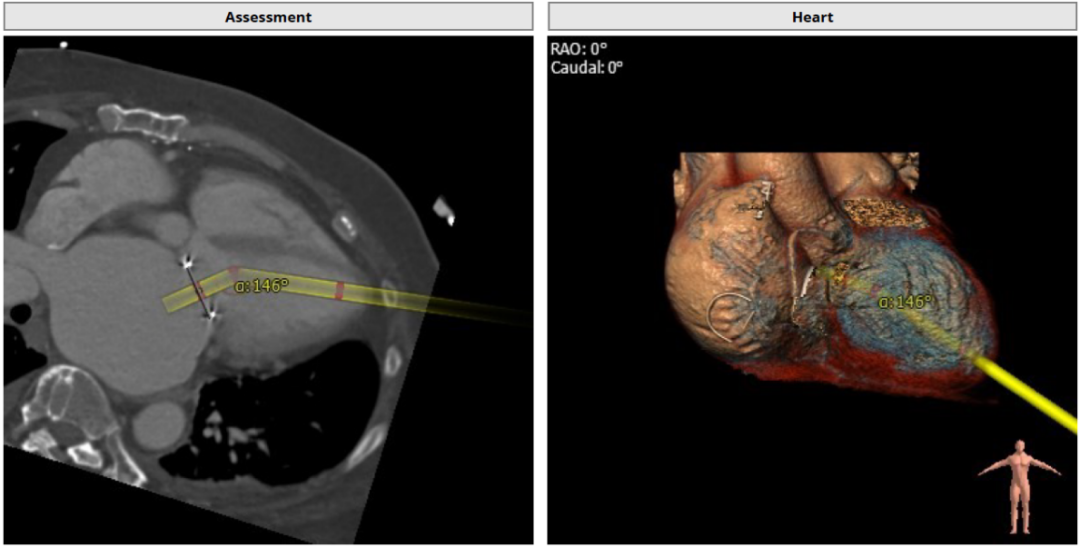

2. AV-MV double S curve :RAO 42°/ CAU 47°,此角度为二尖瓣主动脉瓣最佳观察位;

3. 左心室和二尖瓣轴线角度:146°;

4. 主动脉与二尖瓣角度:133°;

5. 术中最佳投射角度:RAO 37° / CRA 20°;